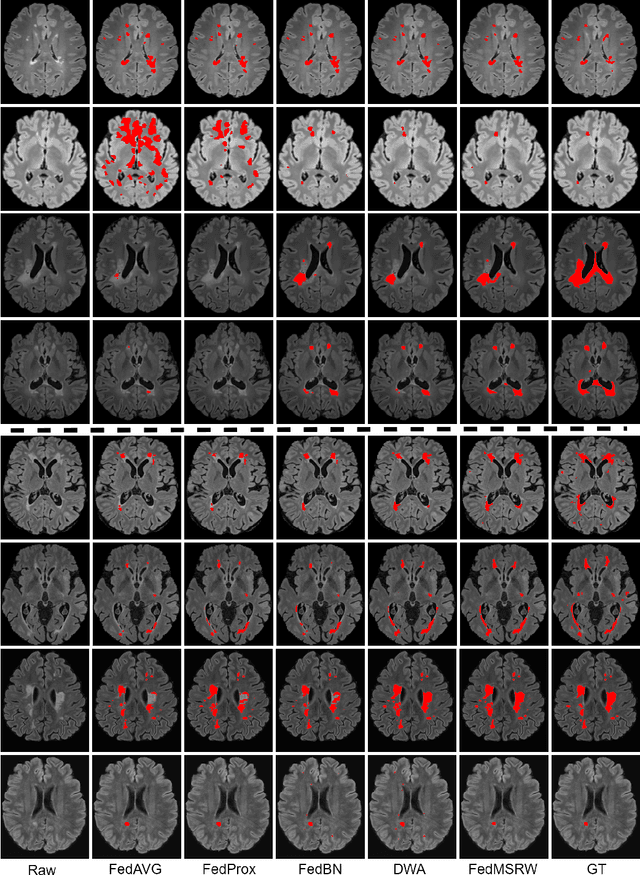

Abstract:Accurately measuring the evolution of Multiple Sclerosis (MS) with magnetic resonance imaging (MRI) critically informs understanding of disease progression and helps to direct therapeutic strategy. Deep learning models have shown promise for automatically segmenting MS lesions, but the scarcity of accurately annotated data hinders progress in this area. Obtaining sufficient data from a single clinical site is challenging and does not address the heterogeneous need for model robustness. Conversely, the collection of data from multiple sites introduces data privacy concerns and potential label noise due to varying annotation standards. To address this dilemma, we explore the use of the federated learning framework while considering label noise. Our approach enables collaboration among multiple clinical sites without compromising data privacy under a federated learning paradigm that incorporates a noise-robust training strategy based on label correction. Specifically, we introduce a Decoupled Hard Label Correction (DHLC) strategy that considers the imbalanced distribution and fuzzy boundaries of MS lesions, enabling the correction of false annotations based on prediction confidence. We also introduce a Centrally Enhanced Label Correction (CELC) strategy, which leverages the aggregated central model as a correction teacher for all sites, enhancing the reliability of the correction process. Extensive experiments conducted on two multi-site datasets demonstrate the effectiveness and robustness of our proposed methods, indicating their potential for clinical applications in multi-site collaborations.

Abstract:Federated learning (FL) has been widely employed for medical image analysis to facilitate multi-client collaborative learning without sharing raw data. Despite great success, FL's performance is limited for multiple sclerosis (MS) lesion segmentation tasks, due to variance in lesion characteristics imparted by different scanners and acquisition parameters. In this work, we propose the first FL MS lesion segmentation framework via two effective re-weighting mechanisms. Specifically, a learnable weight is assigned to each local node during the aggregation process, based on its segmentation performance. In addition, the segmentation loss function in each client is also re-weighted according to the lesion volume for the data during training. Comparison experiments on two FL MS segmentation scenarios using public and clinical datasets have demonstrated the effectiveness of the proposed method by outperforming other FL methods significantly. Furthermore, the segmentation performance of FL incorporating our proposed aggregation mechanism can exceed centralised training with all the raw data. The extensive evaluation also indicated the superiority of our method when estimating brain volume differences estimation after lesion inpainting.